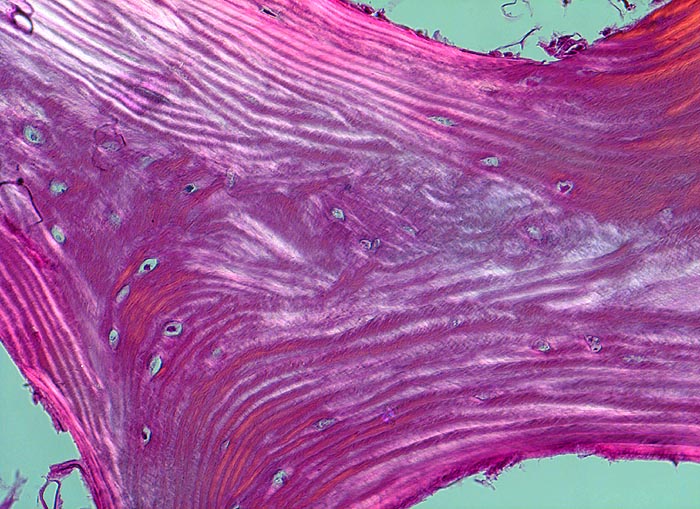

• Tibiametaphyse mit angrenzendem Weichteilgewebe.

• Das Sarkom infiltriert diffus den spongiösen Knochen der Diaphyse und hat präexistente Knochenbälkchen verdrängt.

• Der Tumor hat die Korticalis destruiert und infiltriert die angrenzende Skelettmuskulatur.

• Der Tumor besteht aus neugebildetem bereits verkalktem Knochen oder einem Netzwerk von primitiven Osteoidtrabekeln. Entlang oder innerhalb der Osteoidtrabekel lokalisierte polymorphe Tumorzellen mit ausgeprägten Kernatypien und zahlreichen Mitosen. Leicht verwaschene Kernstrukturen als Folge der Gewebsentkalkung.